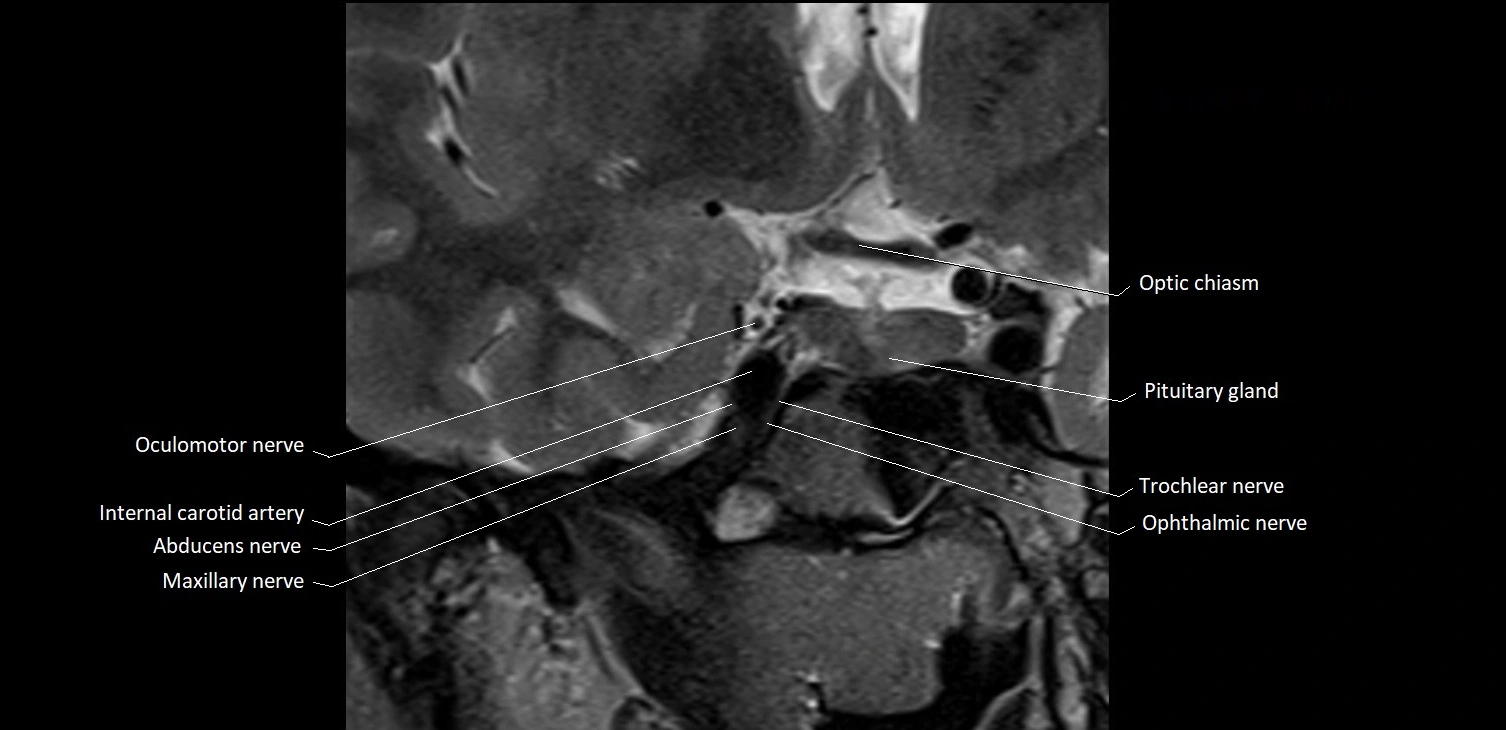

MRI Appearance

The abducens nerve is a small, thin, linear structure

Best visualized on high-resolution T2-weighted 3D MRI sequences (e.g., FIESTA or CISS)

Seen as a hypointense (dark) line running from the brainstem at the pontomedullary junction, traversing the prepontine cistern, and entering Dorello’s canal under the petrosphenoidal ligament, then into the cavernous sinus, and finally the orbit

May be challenging to visualize in standard MRI due to its small size

Pathology may be inferred by absence, displacement, or enhancement of the nerve

MRI images